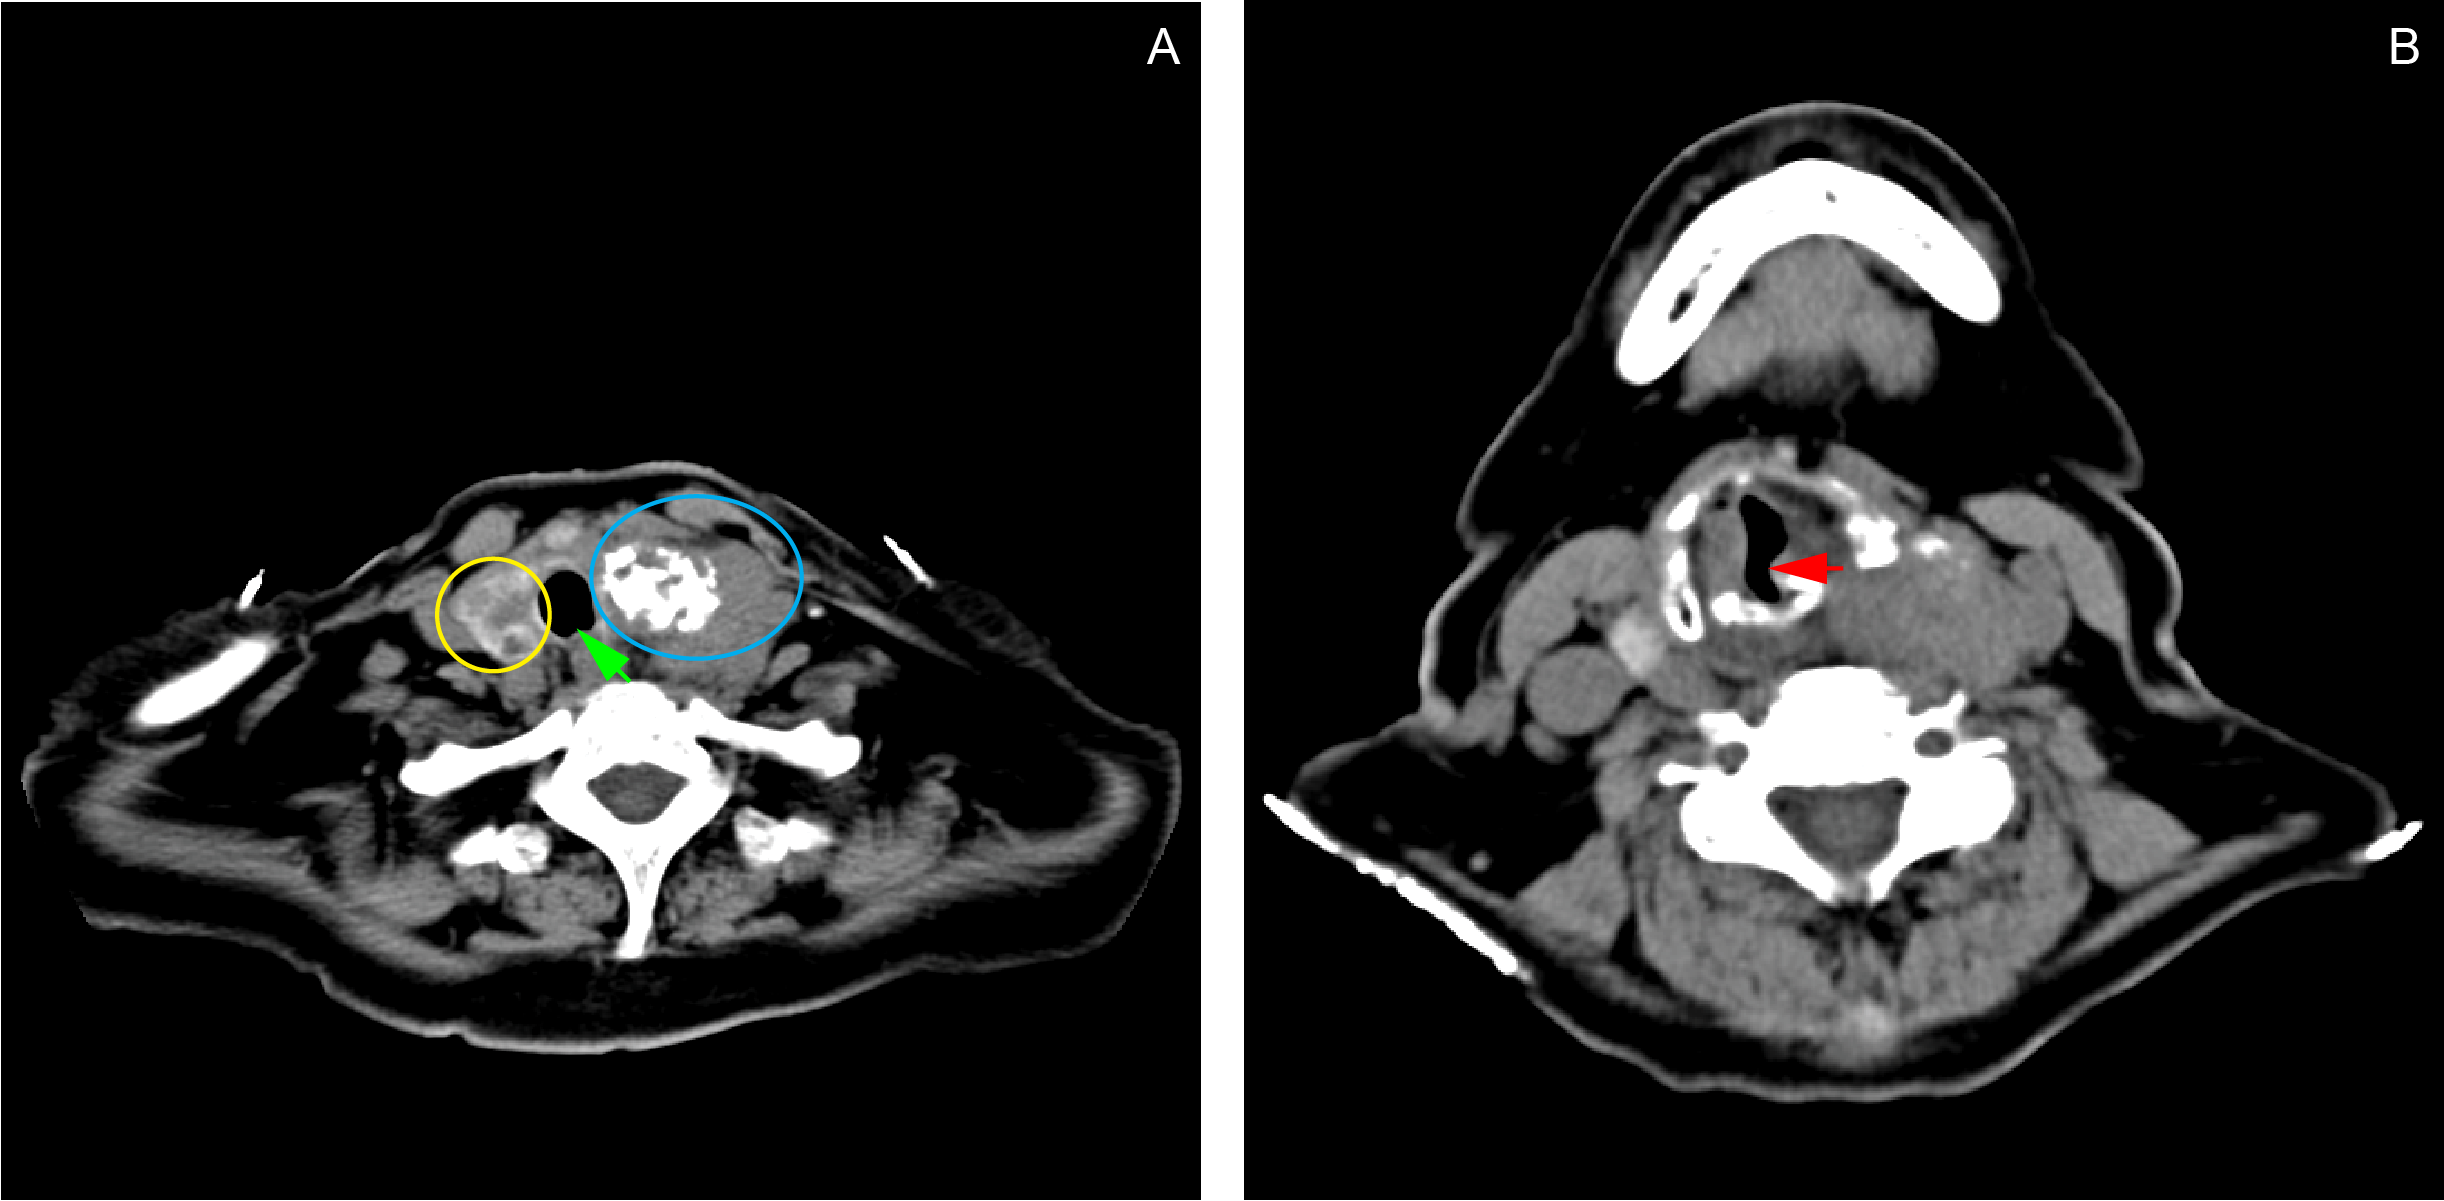

| Figure 2

Contrast chest CT scan showing a fairly-defined, heterogeneously-enhancing lesion (4.41 x 5.31 x 3.89 cm) with internal coarse calcifications seen in the left thyroid lobe (A: blue ring). Soft tissue extension from the thyroid gland into the trachea causes narrowing of the airway at the level of T1 (B: red arrow). The mass also deviates the trachea to the right (A: green arrow). The right thyroid lobe contains multiple subcentimeter, hypodense, non-enhancing, non-calcified lesions (A: yellow ring).

The patient also had a 4-year history of palpable anterior neck mass with no associated symptoms. Two years after the onset of the neck mass, the patient started to have voice hoarseness, which prompted her to seek consultation at our institution’s ENT Department. A contrast neck CT scan done revealed a probably malignant left thyroid mass, multiple thyroid cysts on the right lobe, and a calcified mediastinal node. The results of the FNAB done two years before admission revealed that the mass was a colloid nodular goiter. She was prescribed levothyroxine 25 mcg daily, which she took with good compliance. The patient was advised thyroidectomy, but she refused to go through the procedure. A contrast chest CT scan done prior to this admission showed that the thyroid mass now extended to the trachea, causing a partial airway obstruction. (Figure 2)